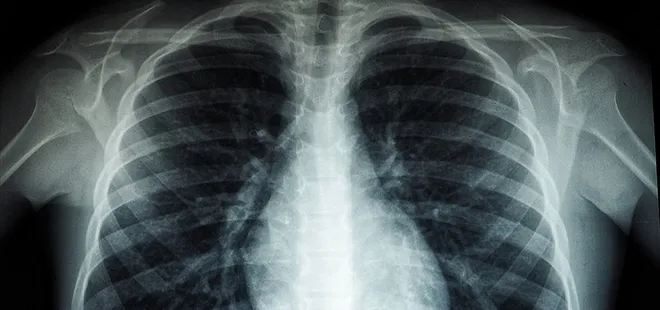

Haberler Sağlık Haberleri Uzmanlar uyarıyor: "Akciğer hastaları yaylalardan uzak durmalı"

Uzmanlar uyarıyor: "Akciğer hastaları yaylalardan uzak durmalı"

Uzmanlar uyarıyor: Akciğer hastaları yaylalardan uzak durmalı

Akciğer hastalarının, havanın daha temiz olduğu düşüncesiyle yüksek rakımlı bölgelere yönelme eğilimi taşıdığına dikkat çeken uzmanlar, bu tercihin her zaman doğru olmadığını vurguluyor.

Konuyla ilgili bilgilendirmede bulunan Karadeniz Teknik Üniversitesi (KTÜ) Farabi Hastanesi Göğüs Hastalıkları Ana Bilim Dalı Dr. Öğretim Üyesi Olcay Ayçiçek, rakım yükseldikçe atmosferdeki oksijen miktarı ve oksijen basıncının azaldığını belirterek bu durumun özellikle kronik solunum hastalıkları olan bireyler için risk oluşturduğunu ifade etti.

Deniz seviyesi daha uygun

Akciğer hastaları için deniz seviyesinin daha uygun olduğunu kaydeden Ayçiçek, "Akciğer hastaları, yüksek rakımlarda havanın daha temiz olduğu düşüncesiyle bu bölgelere çıkma eğilimindedir. Ancak, rakım yükseldikçe atmosferdeki oksijen miktarı ve oksijen basıncı azalır. Deniz seviyesinde oksijen basıncı en yüksek düzeydedir. Bu nedenle, oksijen düşüklüğü ile seyreden akciğer hastalığı olan bireyler için deniz seviyesi daha uygundur" dedi.

Yaş değil, oksijen seviyesi belirleyici

Oksijen seviyesi normal olan bireylerin yüksek rakımlı bölgelere çıkmasında herhangi bir sakınca bulunmadığını belirten Ayçiçek, "Oksijen seviyesi düşük olan ve dışarıdan oksijen takviyesi alması gereken hastaların yüksek rakımlı bölgelerde yaşamasını ya da bu yerlerde uzun süre zaman geçirmesini pek önermiyoruz. Çünkü rakım yükseldikçe oksijen seviyesi azalır ve en yüksek oksijen seviyesi deniz seviyesindedir. Dolayısıyla bu tür hastalar için deniz seviyesi hem daha uygun hem de daha sağlıklıdır. Oksijen seviyesi normal olan hastalar ise sağlıklı bireyler gibi rahatlıkla yaylalara çıkabilirler. Bu konuda belirli bir yaş kriteri yoktur; "Şu yaşın üzerindekiler yüksek rakımlı yerlere çıkmamalı" şeklinde kesin bir kural bulunmamaktadır. Bu tamamen kişinin oksijen seviyesiyle, yani kandaki oksijen düzeyiyle ilgili bir durumdur" diye konuştu.